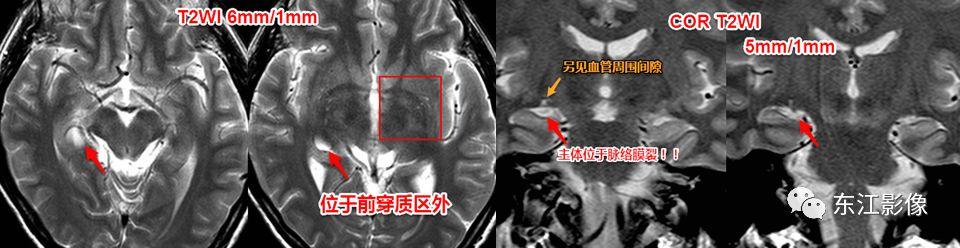

脉络膜裂囊肿

- 定位是其主要依据,冠状面、矢状面有助于区分。

- 脉络膜裂囊肿起自脉络膜裂,更容易沿脉络膜裂延伸、向下压迫海马。

- 而前穿质区扩大的血管周围间隙是起自前穿质区,较大时容易向脉络膜裂方向膨隆,因此脉络膜裂是受压变窄的,且“囊样灶”下方可见残存的“基底节区”脑实质。

脉络膜裂囊肿,与前穿质区扩大的血管周围间隙比较。

前穿质区扩大的血管周围间隙经常被误诊为脉络膜裂囊肿、腔隙性梗死灶。

信号上血管周围间隙与脉络膜裂囊肿没什么差异,形态学有一定的价值。

前穿质区是血管周围间隙最常见的部位,主体位于脑实质,层面合适时可见尖角(==》多方位观察)。

矢状或冠状薄层图像更容易显示向下突出的“残留”的脑实质!这是区分两者的重要影像证据!

脉络膜裂囊肿位于脉络膜裂,先引起脉络膜裂增宽,海马受压;压力大时,才向上压迫前穿质区脑实质。

注意,海马的压力较前穿质区脑实质小得多,所以脉络膜裂囊肿更容易压迫海马,因此主体部位不应是位于前穿质区!